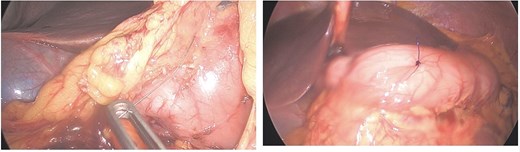

Eventually, diagnostic laparoscopy showed a small posterior gastric perforation next to the liver abscess with migration of the metal bristle into the liver, causing the abscess. Consecutively, surgical drainage of liver abscess, recovery of the foreign body, and gastric perforation repair with sutures were performed (Fig. 4). No postoperative complications occurred. The patient received intravenous antibiotic treatment for 10 days, followed by oral antibiotics for another 4 days. Follow-up showed decreasing CRP and WBC and rapid recovery after surgery. On the 4th postoperative day, the patient could be discharged.